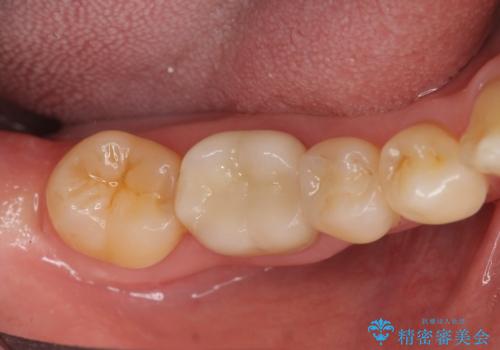

インレーとクラウン 銀歯をセラミックにやりかえ